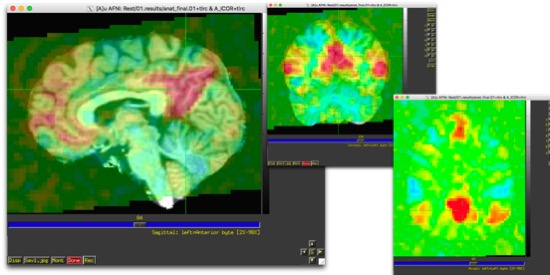

Now, we’re going to start by finding the DMN. It’s one of the most robust resting state networks, so if you can’t find it in your processed data, there’s a good chance something has gone horribly, horribly wrong. I find this by choosing a sagittal slice just off the midline (in about the center of that line of grey matter), and finding where the two marked sulci intersect. They have names, I don’t remember what they are. But, it’s a wiki page, so someone could add them. ctrl-shift-click.

Huzzah!! Now you should have a colored map over your anatomical set. And hopefully, it looks a lot like this:

There should be a big blob near where you clicked, and something else in the front. There shouldn’t be that much outside the head. If you look at other views, it should be largely symmetric, and you should be able to clearly see 4 big blobs, which are generally visible in one axial slice. There should be a big blob where you clicked (there should always be a big blob where you put your seed- it should be strongly correlated to itself.) There should be two near the angular gyri, and one in the medial frontal lobes.

You can now ctrl-shift-click and drag. If you run along an axial or coronal slice, you should be able to see some largely symmetric blobs forming that more/less trace grey matter boundaries. If you pick out some areas of interest to you (motor system, visual system, etc), you should be able to see the rest of the network light up.